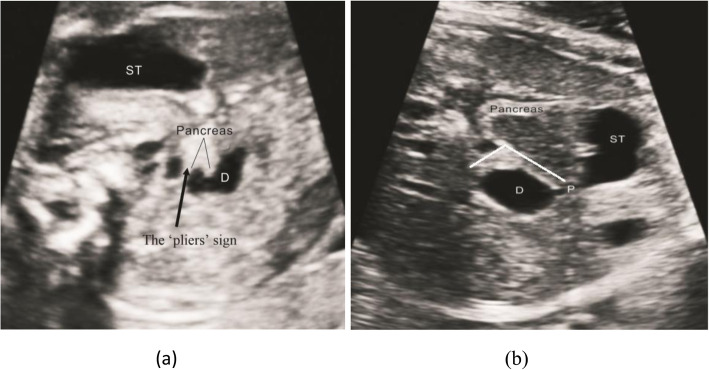

The shape of the head of the pancreas was irregular. A sharp angle was observed between the head of the pancreas and the expanded duodenum, as the bifurcated head wrapped around the ascending or descending part of the duodenum. Moreover, the expanded intestines passed through and wrapped around the pancreas. This appearance on the ultrasound image was similar to a pliers, so we called it the ‘pliers’ sign, as shown in Fig. 6a [9, 10].

a The bifurcation of the head of pancreas is characterized by ‘pliers’ sign. The head of pancreas is hypertrophic and irregular; b. A patient of misdiagnosed duodenal dilatation with ‘rat tail’ sign. The shape of pancreas is regular. The angle between pancreas and duodenum is obtuse. Duodenum (D); Stomach (ST); Pylorus(P)

In this study, 5 patients with annular pancreas were diagnosed by the ‘pliers’ sign, of whom 4 patients were confirmed by operation, 1 patient was misdiagnosed. 1 patient was missed. The specific analysis is shown below.

In CDO caused by annular pancreas, we found that there were common features on prenatal ultrasound images. The head of the pancreas was hypertrophied and irregular in shape. The bifurcation of the head of the pancreas was characterized by the ‘pliers’ sign, wrapping the ascending and descending parts of the duodenum at an acute angle [12]. The structure of the head of the pancreas and the wall of the duodenum were irregular, and the boundary was not clear. Moreover, the head of the pancreas and the dilated duodenum were intertwined (Fig. 6a). However, in duodenal obstruction caused by other reasons, the structure of the pancreas and head of the pancreas were regular, but the structure of the duodenal wall was irregular, as shown in Fig. 6b. Even if the pancreas and head of the pancreas were close to the wall of the pancreas and intestine, the boundary between the pancreas and head of the pancreas was clear, and there was no ‘pliers’ sign showing intertwining. By analyzing the causes of the unclear structure of the head of the pancreas and the duodenal wall, some experts found that the fat gap between the annular pancreatic tissue and the duodenal intestinal wall tissue disappeared because of their interweaving [9]. The anatomy of annular pancreas is shown in Fig. 7. It was confirmed that the diagnosis based on prenatal ultrasound was accurate.

One patient misdiagnosed by operation was shown to have duodenal diaphragm. In a retrospective study of this image, it was found that the angle of the ‘pliers’ sign was obtuse rather than acute. The strongly echogenic wall of the intestine was mistaken for the bifurcated head of the pancreas surrounding the descending part of the duodenum. The structure of the expanded duodenal wall was regular, and the serous layer of the duodenum was intact. Because the expanded duodenum compressed the head of the pancreas, the head of the pancreas was close to the wall of the duodenum. However, the boundary between the two was clear, and the shape of the pancreas was regular, as shown in Fig. 6b.